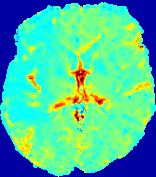

LesionRefer to captionRefer to captionRefer to captionRefer to captionRefer to captionRefer to caption𝐕rgbsubscript𝐕𝑟𝑔𝑏{\bf{V}}_{rgb}Refer to captionRefer to captionRefer to captionRefer to captionRefer to captionRefer to caption𝐕2subscriptnorm𝐕2{\|\bf{V}}\|_{2}Refer to captionRefer to captionRefer to captionRefer to captionRefer to captionRefer to captionRefer to caption3.53.53.52.82.82.82.12.12.11.41.41.40.70.70.70.00.00.0(mm/s)𝑚𝑚𝑠(mm/s)D𝐷DRefer to captionRefer to captionRefer to captionRefer to captionRefer to captionRefer to captionRefer to caption0.0200.0200.0200.0160.0160.0160.0120.0120.0120.0080.0080.0080.0040.0040.0040.0000.0000.000(mm2/s)𝑚superscript𝑚2𝑠(mm^{2}/s)Slice #1Slice #2Slice #3Slice #4Slice #5Slice #6

Figure 4: PIANO feature maps for another patient in the ISLES 2017 training set, where the lesion is located in the right hemisphere. Top row: segmented stroke lesion region (white) on different slices. The corresponding slices for the PIANO feature maps are shown in the following rows.

For a better insight into an estimated velocity field 𝐕𝐕{\bf{V}} and diffusion field 𝐃𝐃{\bf{D}}, we compute the following maps: (1) 𝐕rgbsubscript𝐕𝑟𝑔𝑏{\bf{V}}_{rgb}: Color-coded orientation map of 𝐕=(Vx,Vy,Vz)T𝐕superscriptsuperscript𝑉𝑥superscript𝑉𝑦superscript𝑉𝑧𝑇{\bf{V}}=(V^{x},V^{y},V^{z})^{T}, obtained by normalizing 𝐕𝐕{\bf{V}} to unit length and mapping its 3 components to red, green, blue respectively; (2) 𝐕2subscriptnorm𝐕2\|{\bf{V}}\|_{2}: 222 norm of 𝐕𝐕{\bf{V}}; (3) D𝐷D: scalar field in Eq. 5.

Fig. 3 and Fig. 4 show the PIANO feature maps estimated from two ISLES 2017 patients: all are highly consistent with the lesion in both cases. Details of the blood flow trajectories are revealed in 𝐕rgbsubscript𝐕𝑟𝑔𝑏{\bf{V}}_{rgb} by the ridged patterns and the sharp changes of colors in the unaffected (right) hemisphere, while the flat patterns appearing within the lesion provide little directional information about the velocity and indicate low velocity magnitudes. Velocity magnitudes are more directly visualized via 𝐕2subscriptnorm𝐕2\|{\bf{V}}\|_{2}, from which one can easily locate the lesion where 𝐕2subscriptnorm𝐕2\|{\bf{V}}\|_{2} is low. D𝐷D also indicates lower diffusion values in the lesion, though with less contrast potentially due to the fact that it captures the accumulated effect of CA diffusion at the voxel-level.